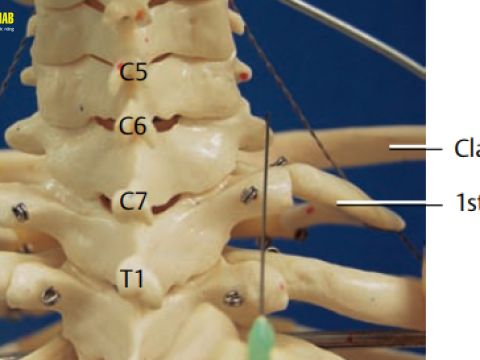

Tiêm cột sống